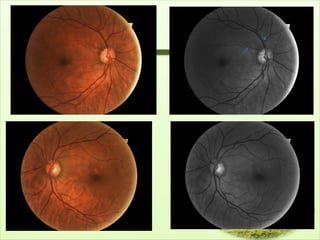

Fundus photography

• RNFL is invisible to red light but easily seen

with short wavelength light..red free light

• Good visualisation is facilitated by clear media,

• RNFL photography-described by Airaksinen &

Nieminen